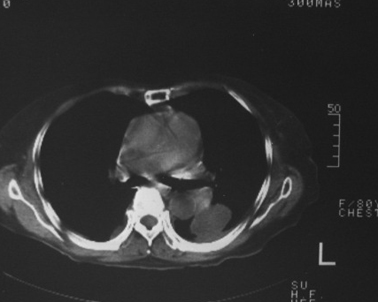

女,80岁,10天前胸片示双下肺感染,正规治疗后复查。体温不高,有脓痰,无臭味。

左肺下叶块影约为17hu!

左下肺片状及块状密度增高影,其内见液化密度影及充气支气管影.考虑炎性病灶,肺脓肿形成

左肺下叶大部实变,内可见含气支气管征。后部见长椭圆形低密度区,周围坏一薄壁。

考虑:左下肺炎症,包裹性胸腔积液。

支持:左肺下叶大部实变,内可见含气支气管征。后部见长椭圆形低密度区,周围环一薄壁,局部胸膜增厚。结合病史考虑:左下肺炎症,包裹性胸腔积液。